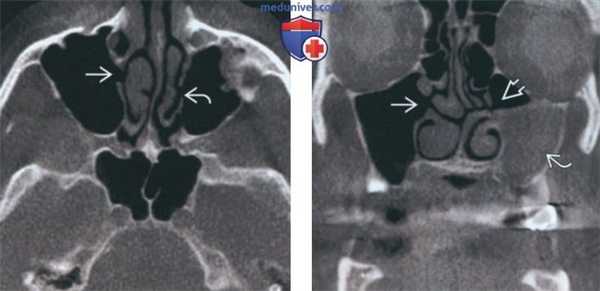

(Слева) На сагиттальной КЛКТ (реконструкций) визуализируется большое куполообразное объемное образование без кортикальной пластинки с плотностью мягких тканей (гиперденсное относительно воздуха), сопоставимое с муцинозной ретенционной псевдокистой верхнечелюстной пазухи. Край пазухи возле кисты интактен.

(Справа) На аксиальной КЛКТ (реконструкция) визуализируется муцинозная ретенционная псевдокиста, занимающая всю камеру правой верхнечелюстной пазухи на этом уровне. Важно не спутать перегородку в пазухе с кортикальной пластинкой на периферии образования. Обратите внимание на утолщение слизистой оболочки камер левой верхнечелюстной пазухи.

(Слева) На периапикальной рентгенограмме задних отделов верхней челюсти справа, не содержащей зубов, на фоне воздуха визуализируется куполообразное затемнение в верхнечелюстной пазухе. Край пазухи возле затемнения интактен. Обратите внимание на наложение скулового отростка.

(Справа) На корональной КЛКТ (реконструкция) визуализируется куполообразная ретенционная псевдокиста в правой верхнечелюстной пазухе. Кортикальная пластинка на периферии псведокисты отсутствует, края пазухи интактны.